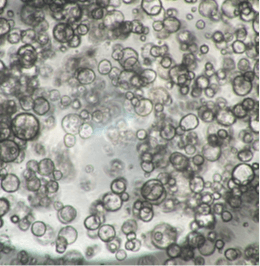

InnoCell(R)プレートシリーズは、体外での細胞培養において、各々の細胞に適した酸素供給を実現できます。その機能により、長期間、元気な細胞を体外で培養できるうえ、スフェロイドの内部で起こる壊死を軽減できるため、正確な医薬品のスクリーニング結果の提供に期待されています。また、これまで体外で培養が難しかった、ヒト膵がん患者由来オルガノイドの増殖性の向上により、個別化医療における患者さんに適した医薬品の早期提供の可能性も期待されています。

さらに、プレートへの薬剤の吸着性が低く、ガラスに匹敵する蛍光観察性能を備えています。試験に供した薬剤が正確に細胞へ作用し、細胞の構造、機能などが可視化できる価値も認められています。